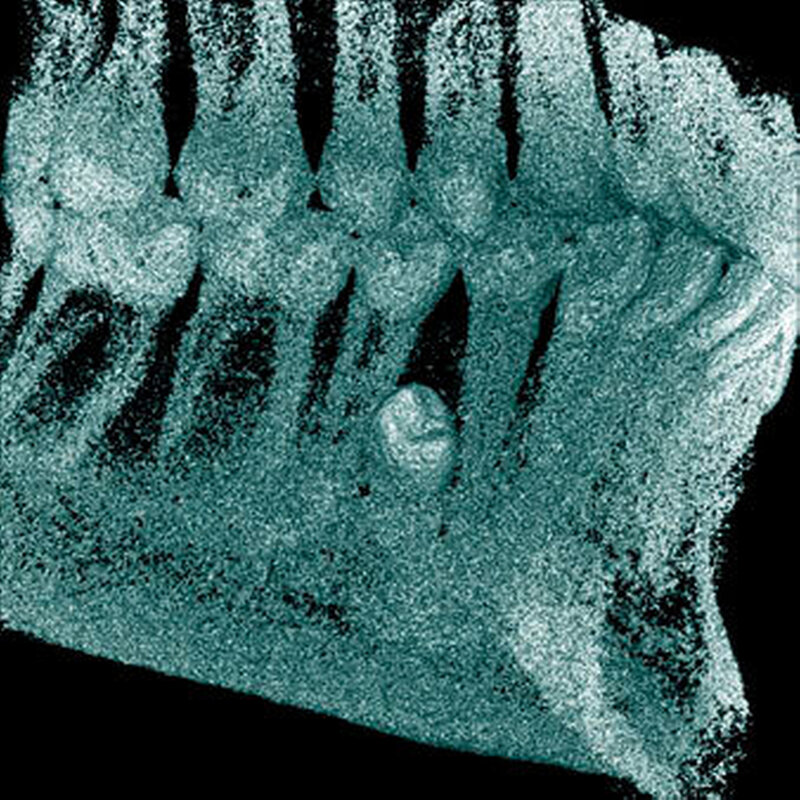

Überzählige Zähne können einzeln oder multipel auftreten [von Arx, 1990; Rajab Hamdan, 2002; Fernández Montenegro et al., 2006; Liu et al., 2007; Gündüz et al., 2008; Ferrés-Padró et al., 2009; Hyun et al., 2009]. Einzelne überzählige Zähne treten in 65,8 bis 80,5 Prozent, doppelte in 14,5 bis 27,7 Prozent und multiple in 0,6 bis 8 Prozent der Fälle auf [Rajab Hamdan, 2002; Fernández Montenegro et al., 2006; Liu et al., 2007; Ferrés-Padró et al., 2009; Hyun et al, 2009; Mossaz et al., 2014]. Einzelne oder doppelte überzählige Zähne finden sich typischerweise in der Oberkieferfront [Rajab Hamdan, 2002; Fernández Montenegroet al., 2006; Mossaz et al., 2014]. Multiple überzählige Zähne werden vor allem im Prämolarenbereich des Unterkiefers gefunden [Abbildung 4; YUSOF 1990, Ferrés-Padróet al., 2009; Wang Fan, 2011]. Multiple überzählige Zähne sind zudem oft mit anderen Erkrankungen oder Syndromen assoziiert, dazu gehören Lippen-Kiefer-Gaumenspalten, die cleidokraniale Dysplasie oder auch das Gardner-Syndrom. Bei Patienten mit einer Lippen-Kiefer-Gaumenspalte wird vermutet, dass sich die überzähligen Zähne aus der Fragmentierung der dentalen Lamina bei der Spaltbildung ergeben [Garvey et al., 1999; Wang Fan, 2011].